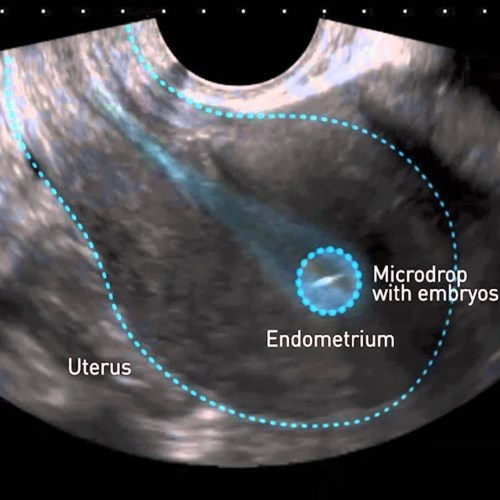

FIVET ICSI

FIVET:

Consiste nella fecondazione naturale dell'ovocita da parte di spermatozoi aggiunti alla cultura in vitro. Le percentuali di fecondazioni degli ovociti Sono inferiori alla fecondazione ICSI

ICSI:

Consiste nell'inserimento introcitoplasmatico di uno spermatozoo scelto dal biologo ed inserito nell'ovocita con l'uso di un apposito ago.